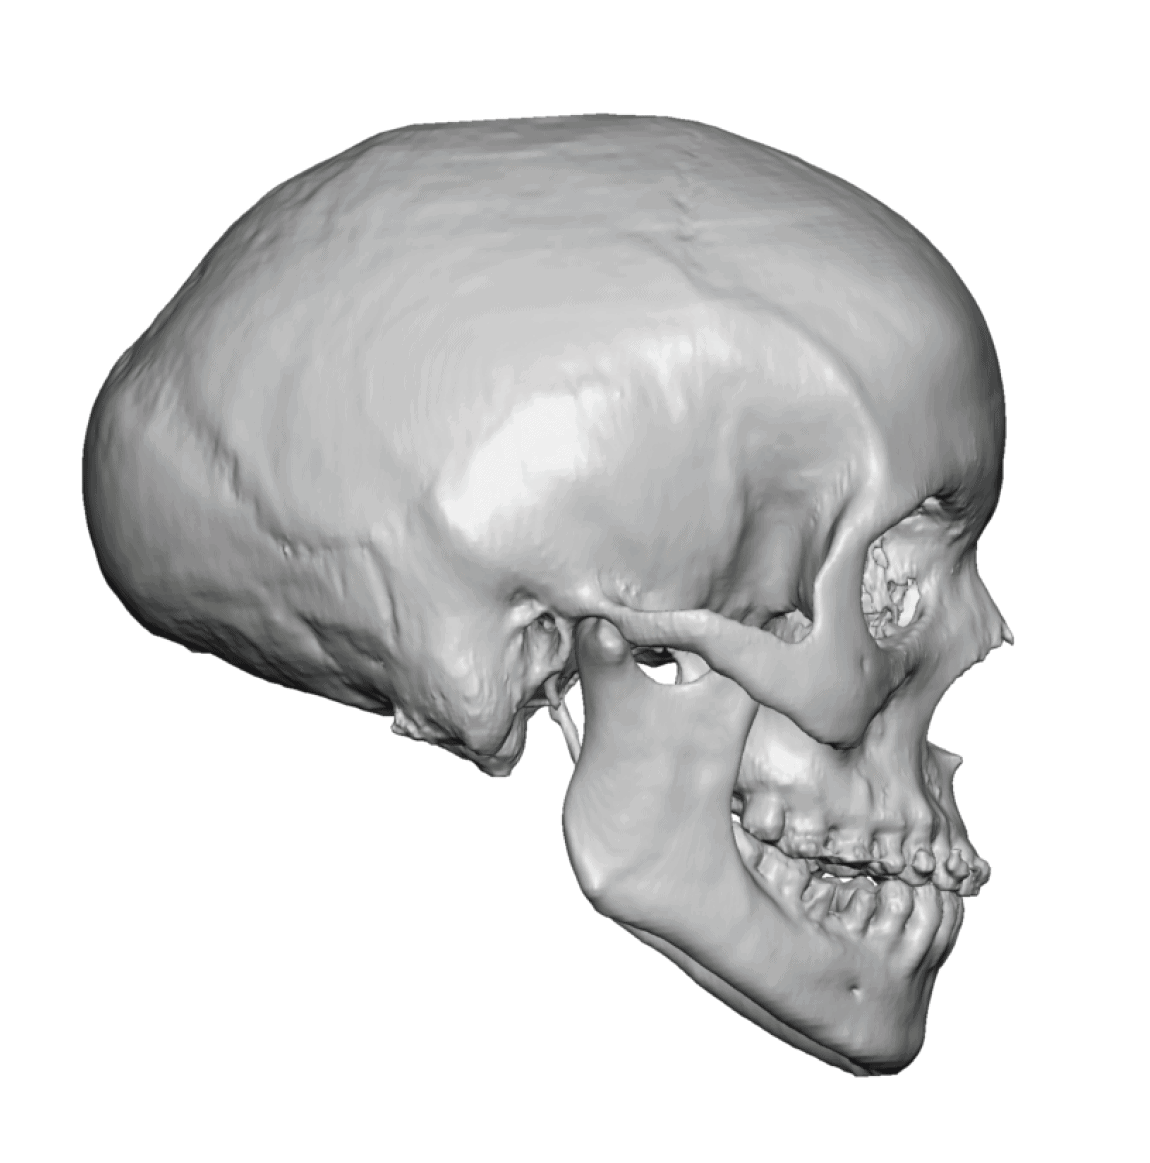

Patient 51

Desire for taller and rounder head shape.

Two stage custom skull implant augmentation technique.

Desire for taller and rounder head shape.

Two stage custom skull implant augmentation technique.